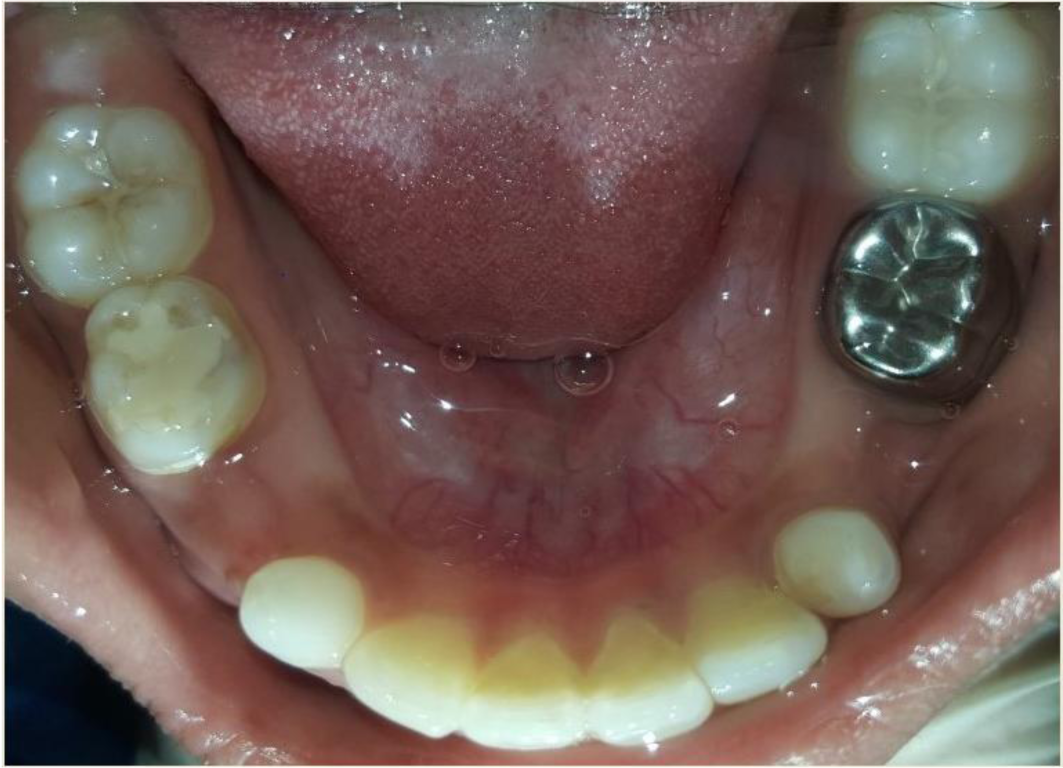

A nine year old boy reported to the Department of Pedodontics and Preventive Dentistry of Bharati Vidyapeeth Deemed University, Sangli with a chief complaint of pain and abscess in the lower left back region of the jaw since one month. Patient was a known case of autism spectrum disorder. He was inattentive, hyperactive and showed repetition of gestures. Psychological testing report showed childhood autism rating scale (CARS) 2, which falls into mild to moderate autistic category. Vineland social maturity scale (VSMS) measuring the social intelligence of child was found to be 31.5 with social age of around 5-6years. The family history was non-contributory. He was not on any medications and had reported no history of drug allergies. Extra-oral examination showed no specific findings (Figure 1). Intraoral examination revealed multiple carious lesions (Figure 2) (Figure 3). Occlusal caries involving enamel, dentin and pulp with 55 and 75. Intra oral dentoalveolar abscess was also seen in relation with 75 (Figure 4). Dentinal caries was seen with 85 and occlusal pit and fissure caries was seen with 65. No soft tissue abnormalities were appreciated. Radiographic evaluation by orthopantomogram was also done which revealed no abnormality (Figure 5). It was difficult for the patient to co-operate on the dental chair and understand the instructions given to him; hence treatment was planned under general anaesthesia. A complete pre anaesthetic evaluation was done and the patient was categorized under ASA II. Treatment plan was explained to the child’s parents and a written consent was obtained from them. The dental treatment done under general anaesthesia included pulpectomy of 55, 75 with glass ionomer cement restoration followed by placement of pre trimmed and pre contoured stainless steel crowns (Figure 6) (Figure 7). Glass ionomer cement restorations were done in 65 and 85 and pit and fissure sealants application on 16, 26, 36 and 46. Post-operative orthopantomogram showed well placed restorations and crowns (Figure 8). Patient’s post-operative recovery was uneventful. Treatment rendered reduced the pain and discomfort.Oral hygiene care instructions were given to the parents and maintenance protocol was explained and they were also encouraged for regular follow-up for preventive dental care. The two months follow-up revealed improved eating habits of the child.

Figure 2 Intra oral pre-operative image of the maxilla.